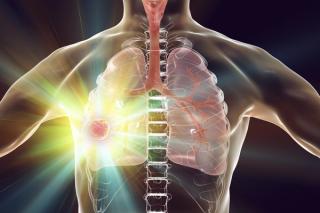

A 40-year-old woman presented with a productive cough and shortness of breath that limited her regular activities. Her past medical history was relevant for hypertension since 2016; it is well controlled and treated with enalapril 5 mg twice daily. She also revealed a past wood smoke exposure of 2 hours per day for 10 years during her childhood.